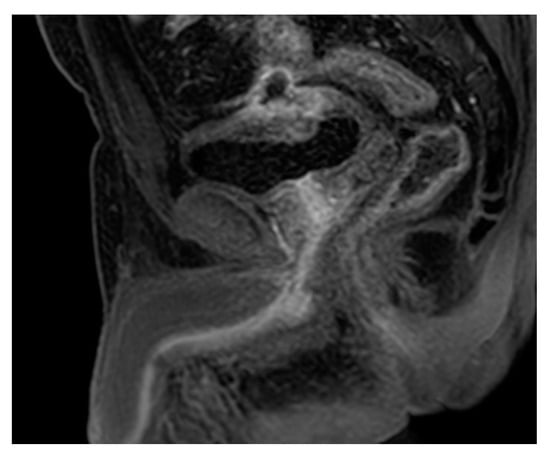

2.15. Acute Bacterial Prostatitis and Prostatic Abscess

- Ren, J.; Huang, X.; Wang, H.; Liu, H.; Ren, F.; Zhang, Z.; Yang, Y.; Yin, H.; Huan, Y. Prostatic abscess and seminal vesicle abscess: MRI findings and quantitative analysis of apparent diffusion coefficient values. Radiol. Infect. Dis. 2015, 2, 27–32. [Google Scholar] [CrossRef]

| Prostatic abscess | Non enhancing fluid collection with peripheral or septal enhancement and non-enhancing central fluid. Possible extraprostatic extension |